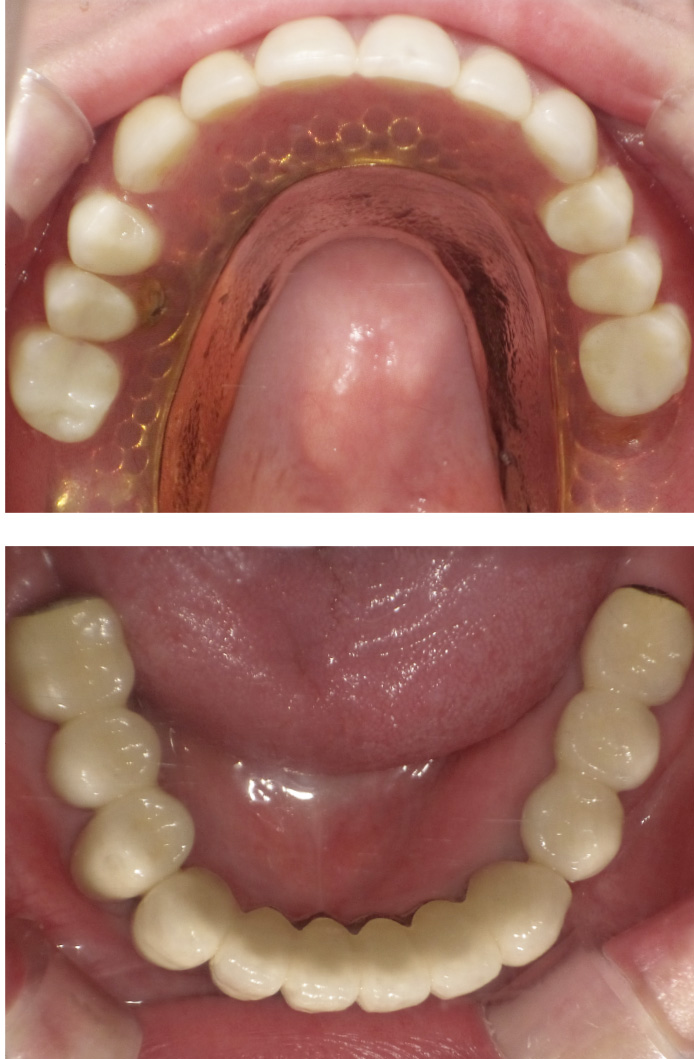

■ 症例紹介(当院の症例)

しっかり噛めるようにしたい(Oさん)

初診時、30代後半でした。残根状態で前歯も動揺あり、どこで咬んでいいのか本人もわからない状態で来院。歯周病もあり下顎前歯は保存不可能でした。

下顎には6本インプラントを埋入してブリッジにしました。上顎は2本インプラントを埋入しロケーター式の無口蓋の義歯にし、少しでも小さい義歯にしてなおかつ外れにくくしました。

● 治療期間/およそ10ヶ月 ●治療回数/10回 ●治療費/およそ600万